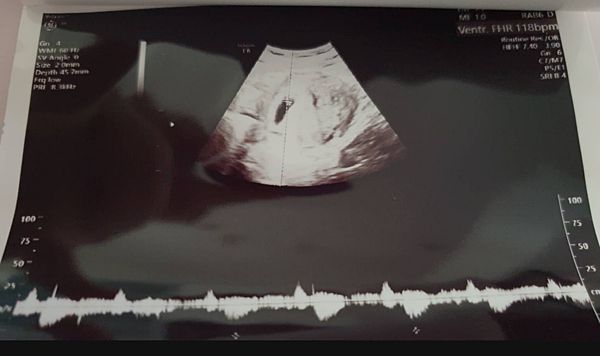

▌第二次產檢(6周) 聽到心跳的瞬間還是很激動 ▌

因為有出血過 所以我也不敢大意

第二次產檢前一天 我根本緊張到睡不著

結果產檢當天 聽到寶寶的心跳

終於讓我心中鬆了一大口氣

因為醫生說 有照到心跳那代表流產機率會降至3-5%

也在當天 我拿到了媽媽手冊

代表我真的是準媽媽了!!